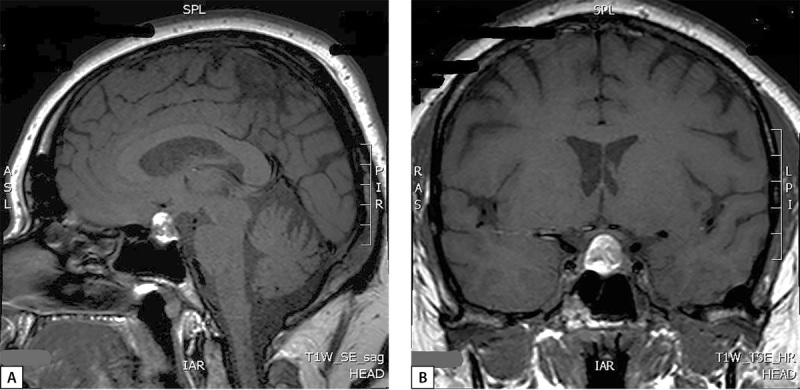

库欣病是一种罕见的严重神经内分泌疾病,由垂体肿瘤长期过度分泌促肾上腺皮质激素引起。内源性高皮质醇症患者体内皮质醇的生理浓度过高,具有类似于全身糖皮质激素治疗的免疫抑制和抗炎作用。这可能会降低患者并发的自身免疫性炎症疾病的活性。另一方面,在治疗库欣病的过程中,皮质醇水平的降低可能与免疫系统的重新激活有关,从而带来自身免疫性疾病发病或复发的风险。我们介绍了自己的一个临床病例,该病例显示,在对库欣病进行手术治疗后,出现了肉样瘤病。

Cushing's disease is a rare severe neuroendocrine disorder caused by chronic overproduction of adrenocorticotropic hormone by a pituitary tumor. Supraphysiological concentrations of cortisol in endogenous hypercortisolism have an immunosuppressive and anti-inflammatory effect similar to therapy with systemic glucocorticosteroids. This may reduce the activity of the patient's concomitant autoimmune inflammatory diseases. On the other hand, a decrease in cortisol levels during treatment for Cushing's disease may be associated with a reactivation of the immune system that pose a risk of onset or recurrence of an autoimmune disorder. We present our own clinical case demonstrating the development of sarcoidosis after surgical treatment of Cushing's disease.